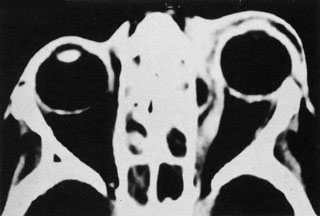

Routine skull films and polytomography have been supplanted by CT in the evaluation of patients with orbital cellulitis.57 CT allows the clinician to differentiate a preseptal cellulitis from an orbital cellulitis.58 If orbital cellulitis has resulted from adjacent intercurrent sinus infection, the diagnosis can be made and the extent of the sinus disease estimated. Sinuses may show changes of osteomyelitis with blurring of the osseous margins of the sinuses, air–fluid levels, or inflammatory tissue within the normally aerated sinus.59 Central nervous system complications can be assessed by neuroimaging, and progression of disease can also be monitored.58

CT should be performed using thin-section (2–4 mm) high-resolution scanning with multiple views of both bone and soft tissue detail.53 Axial and coronal views should be obtained; in one-third of patients with subperiosteal abscesses, the abscess was seen in the coronal sections only.18 Helical CT is a fairly new technology that allows increased resolution with decreased imaging time.60 This type of scan may be especially beneficial in children because of the ability to obtain good imaging with a shorter imaging time.60 elica He HhIntravenous contrast material is not advocated at all centers because there is intrinsically high contrast between infectious changes and orbital fat. However, some authors believe that it is essential to the diagnosis, and it thus remains the preference of the individual clinician, as well as the neuroradiologist.22,59,62

With preseptal inflammation, CT demonstrates soft tissue swelling of the eyelids and tissue adjacent to the orbital septum (Fig. 15). The orbit is not involved, and usually the sinuses do not show evidence of inflammation. The distinction between inflammatory preseptal cellulitis and edema cannot be made.63

Fig. 15. Computed tomography showing preseptal cellulitis of left eye. Note that all swelling is anterior to the orbital septum.